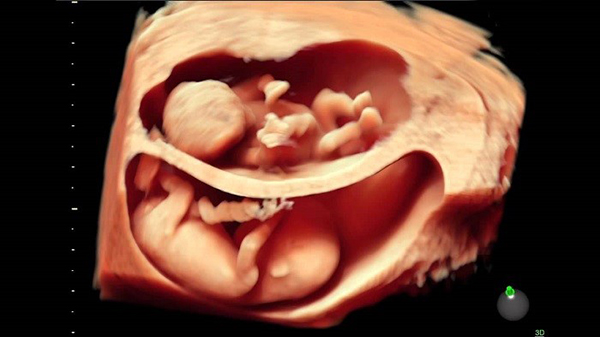

Vào tuần thứ 37, trọng lượng của thai nhi trung bình khoảng 2.8 kg và có chiều dài khoảng 49-50 cm. Dựa vào đường kính lưỡng đỉnh, bác sĩ cũng có thể xác định được tương đối trọng lượng của thai nhi.

Thai nhi 37 tuần tuổi đã bước vào giai đoạn quan trọng, chuẩn bị ra đời. Lúc này thai đã có khả năng dần thích nghi với môi trường bên ngoài bụng mẹ.. Trong thời gian từ tuần 32 trở đi, mẹ bầu cần chú ý thăm khám thường xuyên hơn để theo dõi tình hình thai nhi cũng như dự tính thời điểm sinh chính xác nhất.